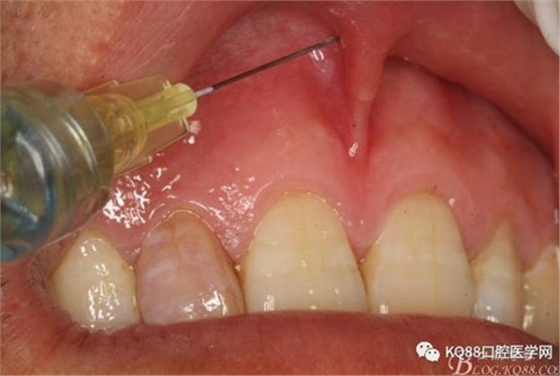

圖4. 唇腭側(cè)局部浸潤(rùn)麻醉行根尖囊腫摘除術(shù)+根管倒充填。唇側(cè)浸潤(rùn)要求進(jìn)針深度比正常麻醉深度要深點(diǎn),因?yàn)檫€有囊腫的摘除。

圖5.腭乳頭浸潤(rùn)麻醉。注意:腭乳頭粘膜發(fā)白即可